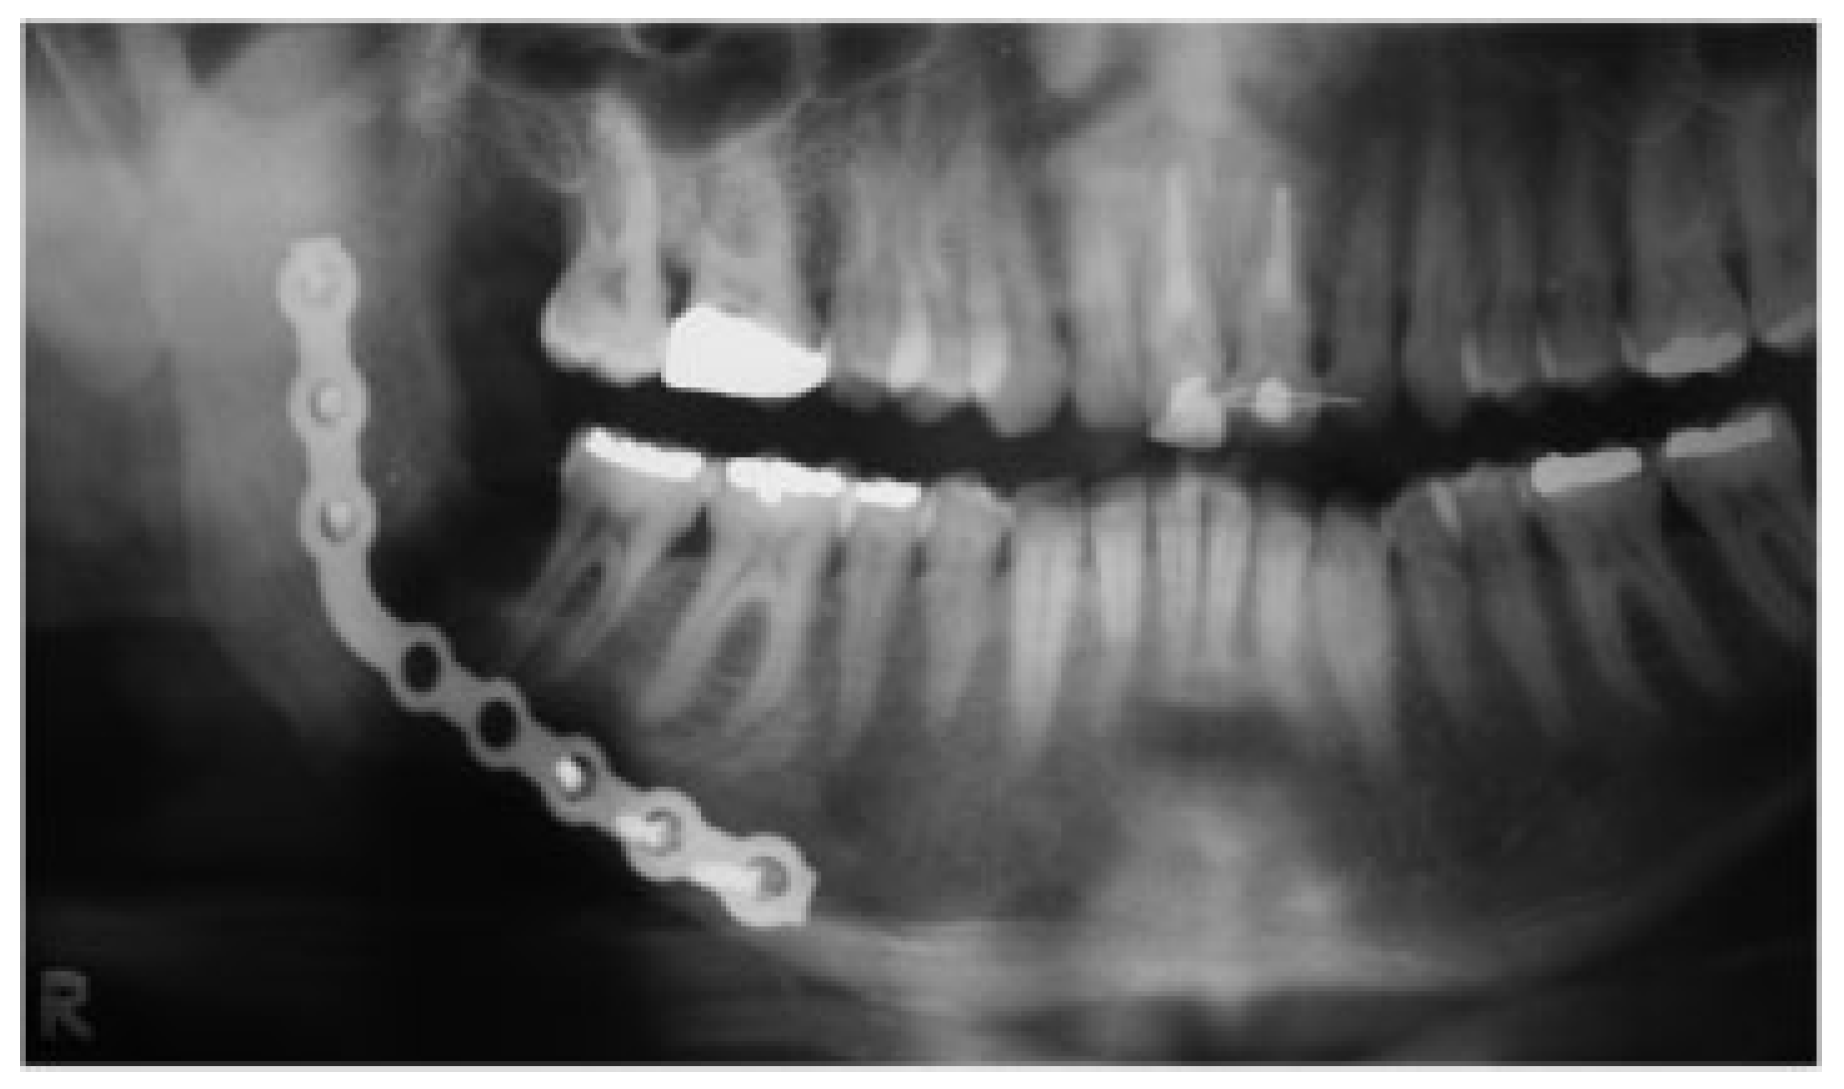

1.1. Case 1